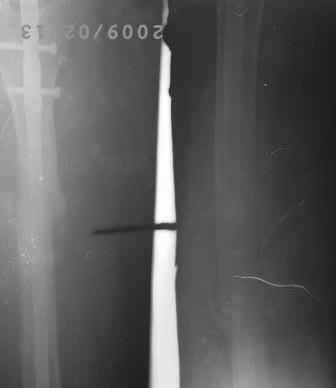

Re: Искривление и/м штифта

12.02.09г б-ная оперирована: з/остеоклазия (без особого труда- видимо тугой ложный сустав) коррекция деформации, удаление штифта из надвертельной обл, рассверливание канала гибкими развертками, реостеосинтез блокируюшим гвоздем Д-11мм.

Но я впервые почувствовал такую сильно ОСТЕОПОРОТИЧНУЮ кость, что блокируюшие винты проваливаются внутрь кости, что винты можно ввести без сверления кости, и что винты провинчиваются холостую, т.е. не стабильно.

P.S. Снимки не качественные, извиняюсь! последний снимок ЭРГА, два снимка объединил.